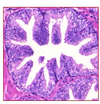

What are the histologic features of prostate adenocarcinoma?

Small glands with an infiltrating pattern

Cells will have prominent nucleoli

No basal cells - they have been lost :(

Staining for basal cells will be negative